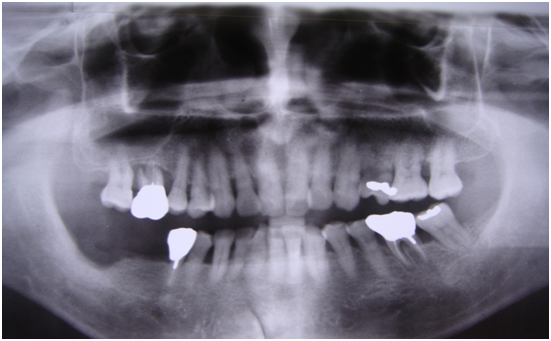

患者的原始片 91/06/13

患者陳先生於91/06/03初診,為一個牙周病患者,合併有右下缺牙。經過保守性牙周處理後,於91/08/14放置右下三顆植體。